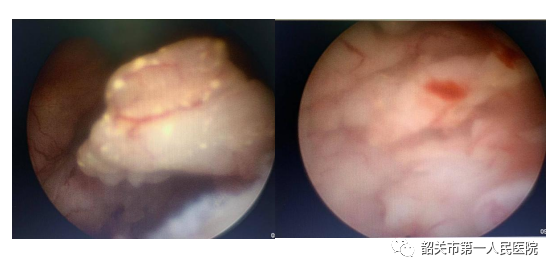

下图为内镜下见宫颈外口赘生物

阴道内镜检查无需使用窥器,而正常女性的生理结构,处女膜孔是可以通过阴道内镜而不受伤害的。我们置镜通过处女膜中间孔缓慢进入阴道,顺着自然腔道轴向缓慢探查阴道,在宫颈外口见到了大小约1.5cm×1cm的息肉样赘生物,蒂长约2.5cm,蒂部位于宫颈管上段,而阴道壁及宫腔内是无异常的。这让我们终于找到了患者异常出血的原因。在阴道内镜下,我们同时摘除了宫颈管息肉。检查与治疗一站式完成,大大减少了患者的痛苦及医疗费用,并且保留了处女膜的完整。